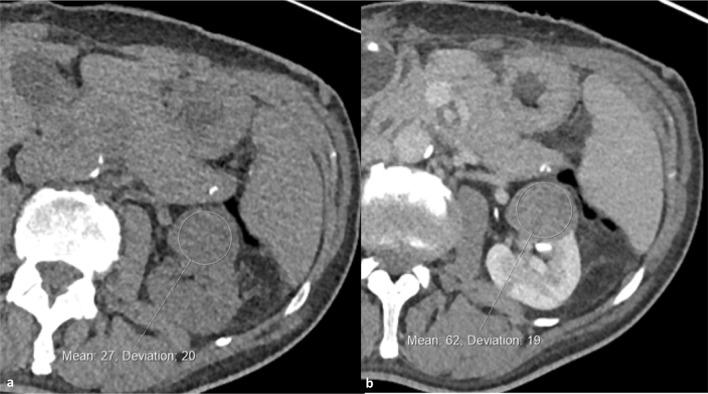

RESULTS

Characterisation of small renal masses (SRM) remains a diagnostic conundrum. Contrast-enhanced ultrasound (CEUS) has been increasingly applied in this field, as have emerging technologies such as multiparametric MRI, radiomics and molecular imaging with technetium-sestamibi single photon emission computed tomography/CT. CT remains the first-line modality for staging of locoregional and suspected metastatic disease. Although the staging accuracy of CT is good, limitations in determining nodal status persist. Response assessment following ablative therapies remains challenging, as reduction in tumour size may not occur. The pattern of enhancement on CT may be a more reliable indicator of treatment success. CEUS may also have a role in monitoring response following ablation. Response assessments following anti-angiogenic and immunotherapies in advanced RCC is an evolving field, with a number of alternative response criteria being proposed. Tumour response patterns may vary between different immunotherapy agents and tumour types; thus, future response criteria modifications may be inevitable.